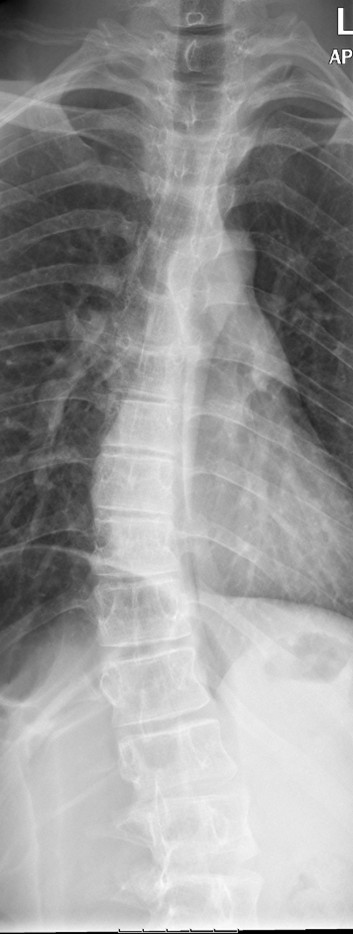

AP x-ray of the spine shows dorsal and lumbar dextroscoliosis (Figure 2).